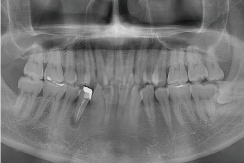

X線

歯周病検査

歯科用CTによる3D画像診断